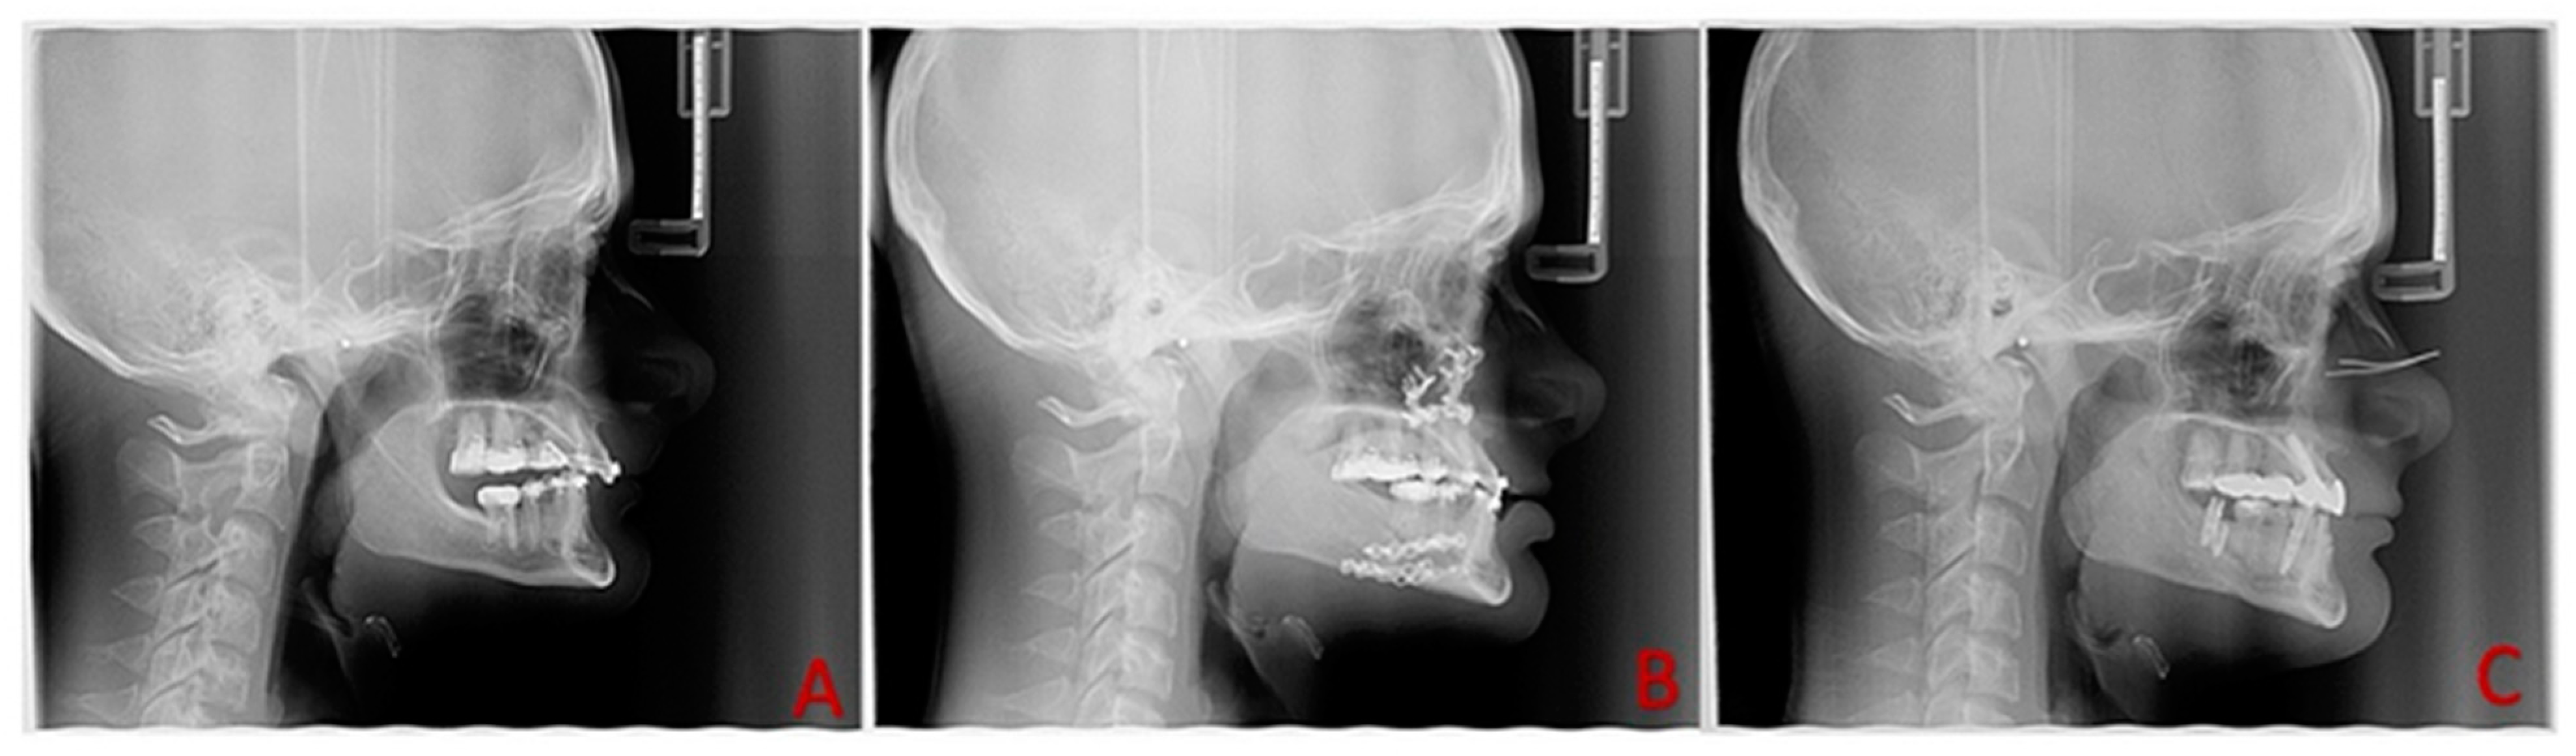

| SNA (°) | the angle between Sella–Nasion–point A |

| SNB (°) | the angle between Sella–Nasion–point B |

| ANB (°) | the angle between point A–Nasion–point B |

| Mandibular length (mm) | the linear distance from Gonion to Menton |

| Sagittal mandibular position (°) | the angle between Sella–Nasion–Pogonion |

| Mandibular plane (°) | the angle between the anatomic Frankfurt horizontal plane and the line drawn along Gonion and Menton |

| Saddle angle (°) | the angle between the anterior and posterior cranial base |

| Gonial angle (°) | the angle between ramus height and mandibular plane (Ar-Go-Me) |

| Articular angle (°) | the angle between the posterior cranial base and ramus height (S-Ar-Go) |

| Sum int angles (°) | sum of angles (Saddle angle + Articular angle + Gonial angle) |

| Y-axis to SN (°) | the angle connecting Gnathion–Sella–Nasion |

| Posterior face height (mm) | the linear distance from Sella to Gonion |

| Anterior face height (mm) | the linear distance from Nasion to Menton |

| Jarabak ratio (%) | the ratio of the Posterior and Anterior facial height |